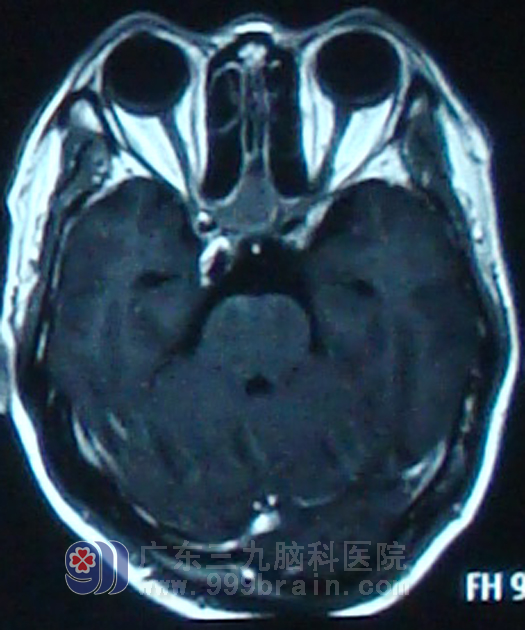

48岁的成先生今年于2年前无明显诱因出现头痛,钝痛,以枕部明显,2月开始出现了右耳听力下降,4月进而出现视物重影,曾按眼疾给予治疗,但未见明显效果。2010年在我院被诊断为鼻咽癌IV期。

因肿瘤巨大,在制定治疗方案时确定先为其行一程诱导化疗,化疗结束后行鼻咽适形调强放疗,放疗期间行同步化疗。治疗期间成某视物重影及右耳听力逐渐好转。 放疗结束后继续行4程辅助化疗。治疗后颈部肿大淋巴结基本消失。目前随访2年,成先生一般情况正常,复查MR未见肿瘤复发征象。www.999brain.com

治疗前